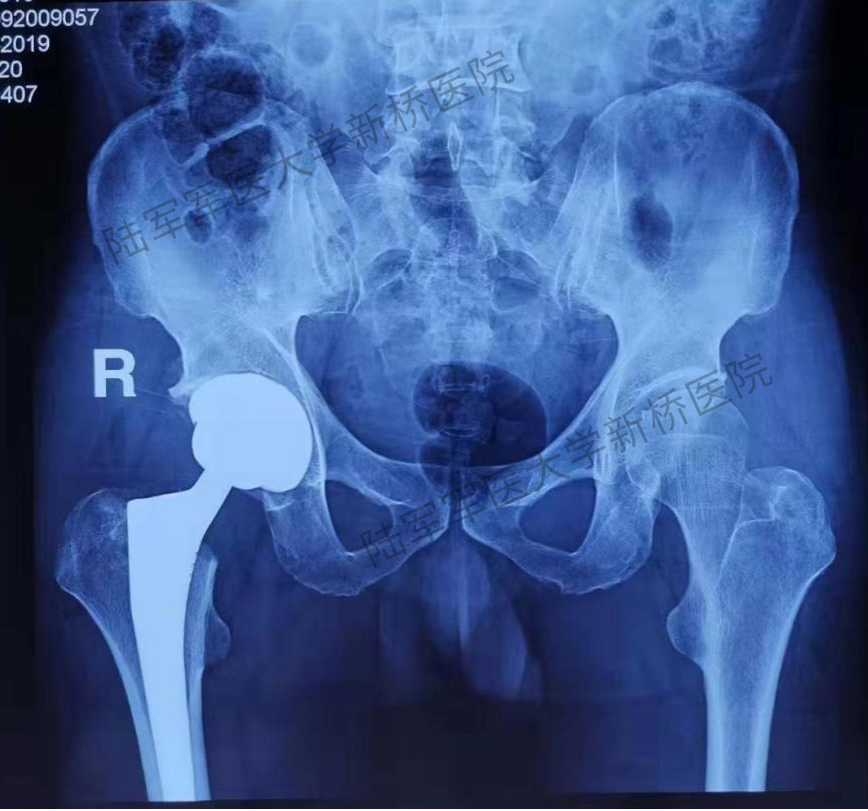

患者术前骨盆前后位X线片

对患者骨盆正位、特别是双侧髋关节局部特征进行观察,此例手术存在较多的骨性和软组织性陷阱。其一,患者为冠状面的双侧髋外翻畸形,双侧CCD角度高达148°,远远超出正常髋关节的生理范围。目前常规股骨假体最大的CCD角也仅有137°,个体化髋关节重建难度高。其二,右侧髋关节因骨性撞击导致股骨头粗大(左侧股骨头直径46mm,右侧股骨头直径54mm),由此导致髋关节周围关节囊360°膨胀性拉长,由此导致髋关节静态稳定结构松弛,术后脱位风险增加!其三,髋臼硬化、形变严重,术中髋臼解剖旋转中心处打磨容易出现偏差。其四,最棘手的是由于撞击导致外展肌过度延长,最终结果是右侧的髋臼偏心距和股骨偏心距均显著外移,由此带来髋关节动态稳定肌群的松弛和菲薄,术后脱位风险进一步增加!在如上困境中,选择常规假体进行手术,往往出现两个极端:要么下肢延长,要么关节脱位。常规术前计划系统,如等比例胶片法、或基于二维X线的计算机软件测量系统,均难以在两者间实现平衡。而基于人工智能深度学习技术与手术模拟算法、图像算法结合,依靠计算机辅助的方式来实现关节置换手术的三维术前规划--AI HIP系统,是解决上述问题的理想选择。

患者术后X线片